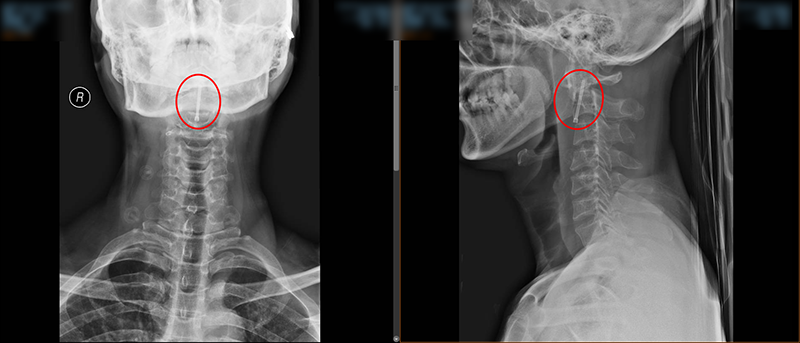

术中,脊柱外科团队对王先生颈部重要的组织结构均进行了较好的保护,而且一次性成功的置入空心拉力螺钉固定骨折断端。手术持续了45分钟,术后王先生颈部疼痛明显缓解,无神经损伤。术后给予抗炎、补液等治疗,在科室专业医疗、护理团队的共同努力下,术后复查X线显示齿状突复位,螺钉位置良好,目前已在支具辅助下行走活动,患者及家属对手术效果非常满意。

▲术后X线检查结果